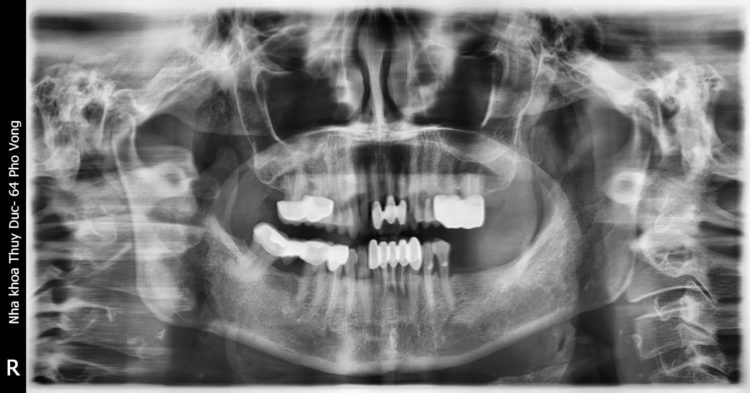

Chụp X – quang răng toàn hàm: Phim chụp X – quang toàn hàm sẽ được bác sĩ sử dụng để đánh giá tổng quan về các mối liên hệ giữa răng, xương hàm và hệ thống dây thần kinh mọc xung quanh răng. Bên cạnh đó cũng giúp bác sĩ xác định được tình trạng răng mọc ngầm dưới nướu, hoặc răng khôn mọc lệch để có phương án điều trị tốt nhất.

Chụp X – quang răng mặt nghiêng: Thông qua phim chụp nghiêng, bác sĩ sẽ phân tích các góc độ về xương, răng, mô mềm, đánh giá được sự tương quan giữa hai hàm trên dưới, giữa hàm và răng cũng như cả mối tương quan với xương sọ.